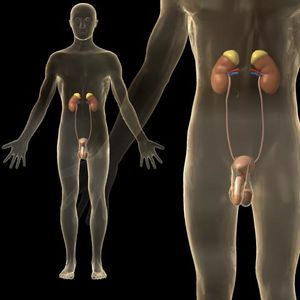

الجهاز التناسلي في الذكر بالإنجليزية Male reproductive system ، هو مجموعة الاعضاء في جسم الذكر التي تلعب دورا في عملية التكاثر الجنسي.

تركيب الجهاز التناسلي الذكري

- كيس الصفن والذي يضم الخصيتين وهي المنتجة للحيوانات المنوية.

- القنوات التناسلية التي تتكون البربخ متصل بوعاء ناقل يصل بدوره إلى الإحليل.

- الغدد التناسلية وتضم كل من الحوصلة المنوية والبروستاتا وغدة كوبر والتي تقوم معا بتكوين بقية مكونات السائل المنوي أو تقوم بوظائف مساعدة.

- الأعضاء التناسلية الخارجية المساعدة، متمثلة بالقضيب والتي تنحصر مهمتها في إيصال الحيوانات المنوية إلى الرحم الإنثوي عن طريق الإيلاج.

يتكون الجهاز التناسلي في الذكر من خصيتين يحاط كل منهما بكيس الصفن الذي يتدلى خارج تجويف البطن , ويخرج من كل خصية قنوات البربخ وكذلك الوعاء الناقل الذي يؤدي إلى الحوصلة المنوية التي يختزن بها الحيوانات المنوية . كما توجد غدد ملحقة بالجهاز التناسلي حتى مجرى البول